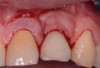

The entry of inflammatory cell infiltrate into the connective tissue (Figure 1 and Figure 2) differentiates peri-implantitis from peri-implant mucositis.1 Unlike a natural tooth—where periodontal fibers, transepithelial fibers, and gingival fibers absorb this exudate—none of these fibers are present around an implant (Figure 3). This allows the inflammatory cell exudate to directly enter the bone, resulting in bone loss and concomitant soft-tissue loss (Figure 4).1

Fig 4. The result of exudate entering the bone surrounding an implant is bone loss and concomitant soft-tissue loss.

Figure 4